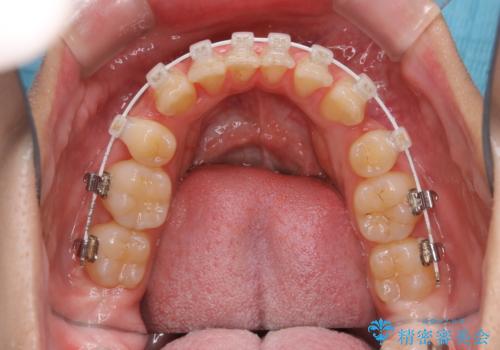

ワイヤー矯正中のクリーニング

- ワイヤー矯正中に、磨ききれないところがあるのと、口臭が気になるとのことでした。

そのためPMTC30分コースを行いました。

ワイヤー矯正中は、装置の周りに汚れが付きやすく虫歯や歯周病のリスクが高まります。そのため、ワイヤー調整の診察の際、一緒にクリーニングを行うことで、虫歯・歯周病・口臭予防になります。歯ブラシだけでは取り除くことが難しい細かい部分などに、専門的な機械や機材を使用して定期的なケアを行うことをおすすめしています。